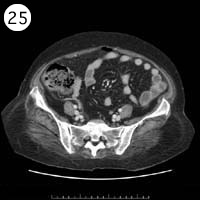

57歳 女性

単純CT

造影CT